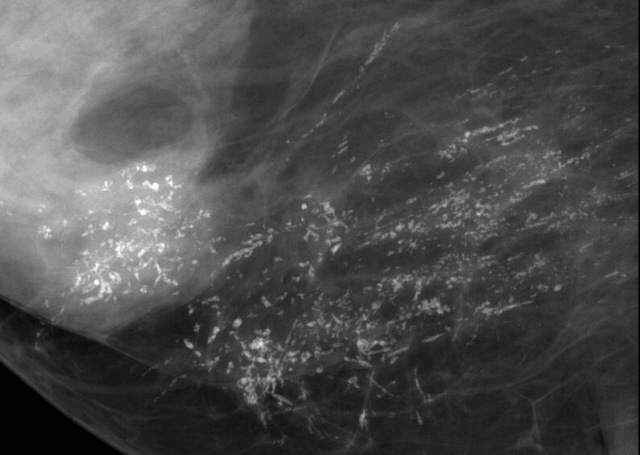

Дуктография — контрастная рентгенография, дающая возможность выявлять мельчайшие новообразования, их локализацию и оценивать их злокачественность или доброкачественность, а также объем необходимого оперативного вмешательства.